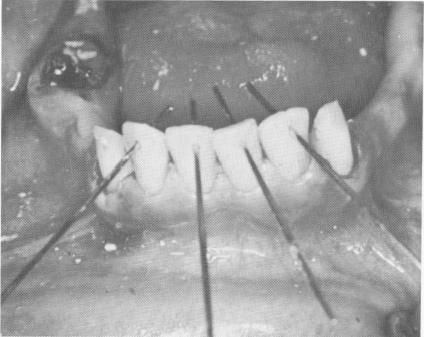

Fig. 11-86. The pins should be adjusted so that they fit flush with the lingual aspects of the anterior teeth.

2 Pins adjusted to fit flush with lingual aspects of anterior teeth